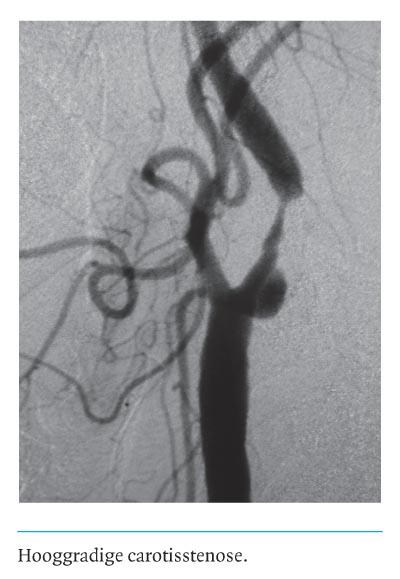

Chirurgische behandeling van de symptomatische carotisstenose: wie en wanneer?

Hoewel gerandomiseerde trials het nut van chirurgische behandeling van de symptomatische carotisstenose > 70 hebben bewezen, hebben subanalyses aangetoond dat de effectiviteit onder andere afhangt van de juiste patiëntenselectie en het tijdstip waarop de ingreep wordt verricht. Rothwell bespreekt in een recent overzichtsartikel de 3 belangrijkste vragen: (a) wat is de…